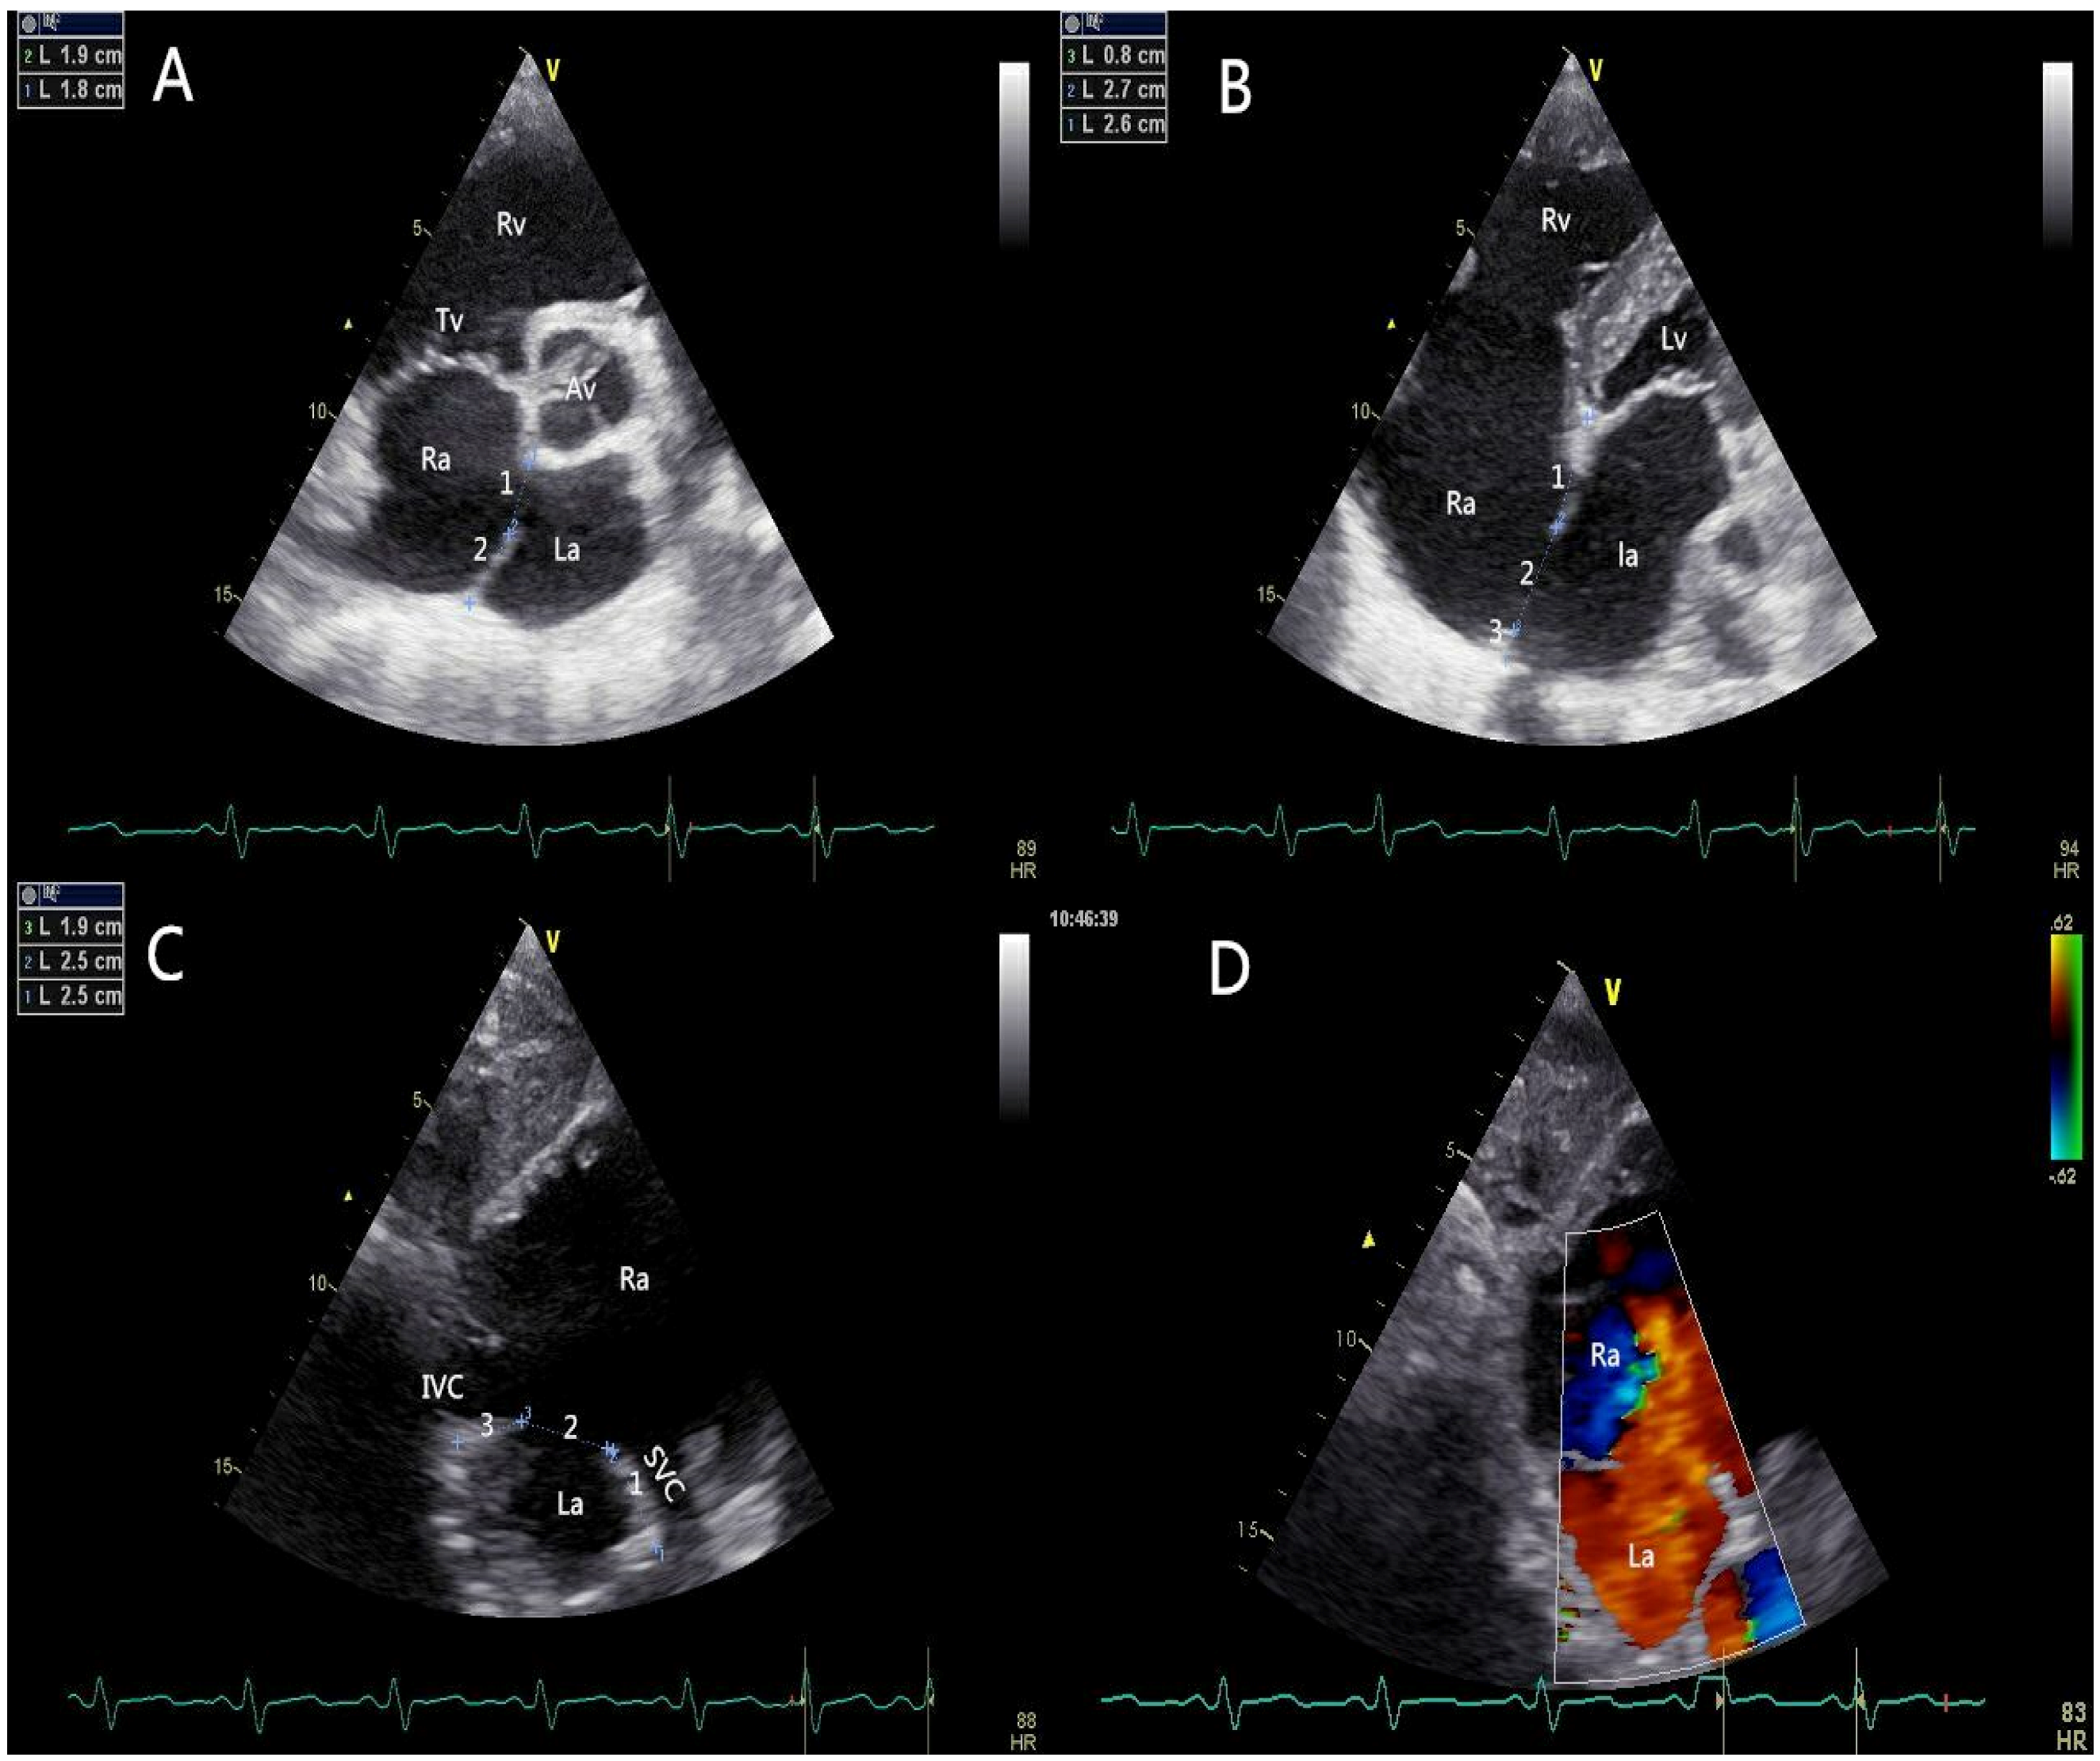

All patients should be evaluated using TTE in terms of defect size, location, rims, adjacent structures, and cardiac function. The edge of the defect was divided into six areas according to their locations or neighboring structures (Figure 2): upper rim (Up-r), atrioventricular valve rim (AVV-r), aortic rim (Ao-r), posterior rim (Po-r), SVC rim (SVC-r), and IVC rim (IVC-r). A floppy septum was considered a normal rim. A “Union Score” was utilized to select patients who were suitable for PAC (Table 1).

Figure 2.

Pre-procedural transthoracic echocardiographic assessment. (A) The short-axis left parasternal view of aortic valve delineated the aortic rim and the posterior rim of the defect; (B) The four-chamber view showed the atrioventricular valve rim and the upper rim; (C) The short axis subcostal view showed the SVC rim and IVC rim; (D) The short axis subcostal view (coloured) showed the blood flow cross the atrial septum (left to right). AV: aortic valve; RA: right atrium; LA: left atrium; RV: right ventricle; LV: left ventricle; TV: tricuspid valve; IVC: inferior vena cava; SVC: superior vena cava.

The figure shows the transthoracic echocardiographic view of ASD without an aortic rim in a 73-year-old patient (Union Score = 0 + 3 + 3 + 2 + 3 + 3 = 14 points). The short-axis left parasternal view of the AV delineated the entire length of the ASD (3A-1), the aortic rim (deficient, 0 points), and the posterior rim (3A-2, 19 mm, 3 points). The four-chamber view shows the atrioventricular valve rim (3B-3, 26 mm, 3 points) and the upper rim (3B-1, 8 mm, 2 points), and the maximum length of the ASD (3B-2) could be observed in this view. The short-axis subcostal view shows the length of the defect (3C-2), the SVC rim (19 mm, 3 points), and the IVC rim (25 mm, 3 points). The figure shows the transthoracic echocardiographic view of the ASD with an adequate SVC rim and an adequate IVC rim. The short-axis subcostal view (colored) shows the blood flow across the atrial septum (left to right) (3D).

In addition, the anomalous pulmonary venous connection should be excluded, especially for ASDs with a short IVC-r. The severity of pre-procedural valve regurgitation was assessed using color flow Doppler. Prominent eustachian valve tissue on the right side of the atrial septum that would interfere with the catheter’s position and device placement was noted and communicated to the cardiac interventionalists.